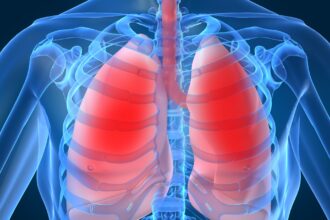

🏃 Treinar em Jejum Emagrece? A Ciência Explica a Oxidação de Gordura

A prática de se exercitar em jejum é popular no universo fitness, mas um estudo recente, realizado por Aird, Davies…